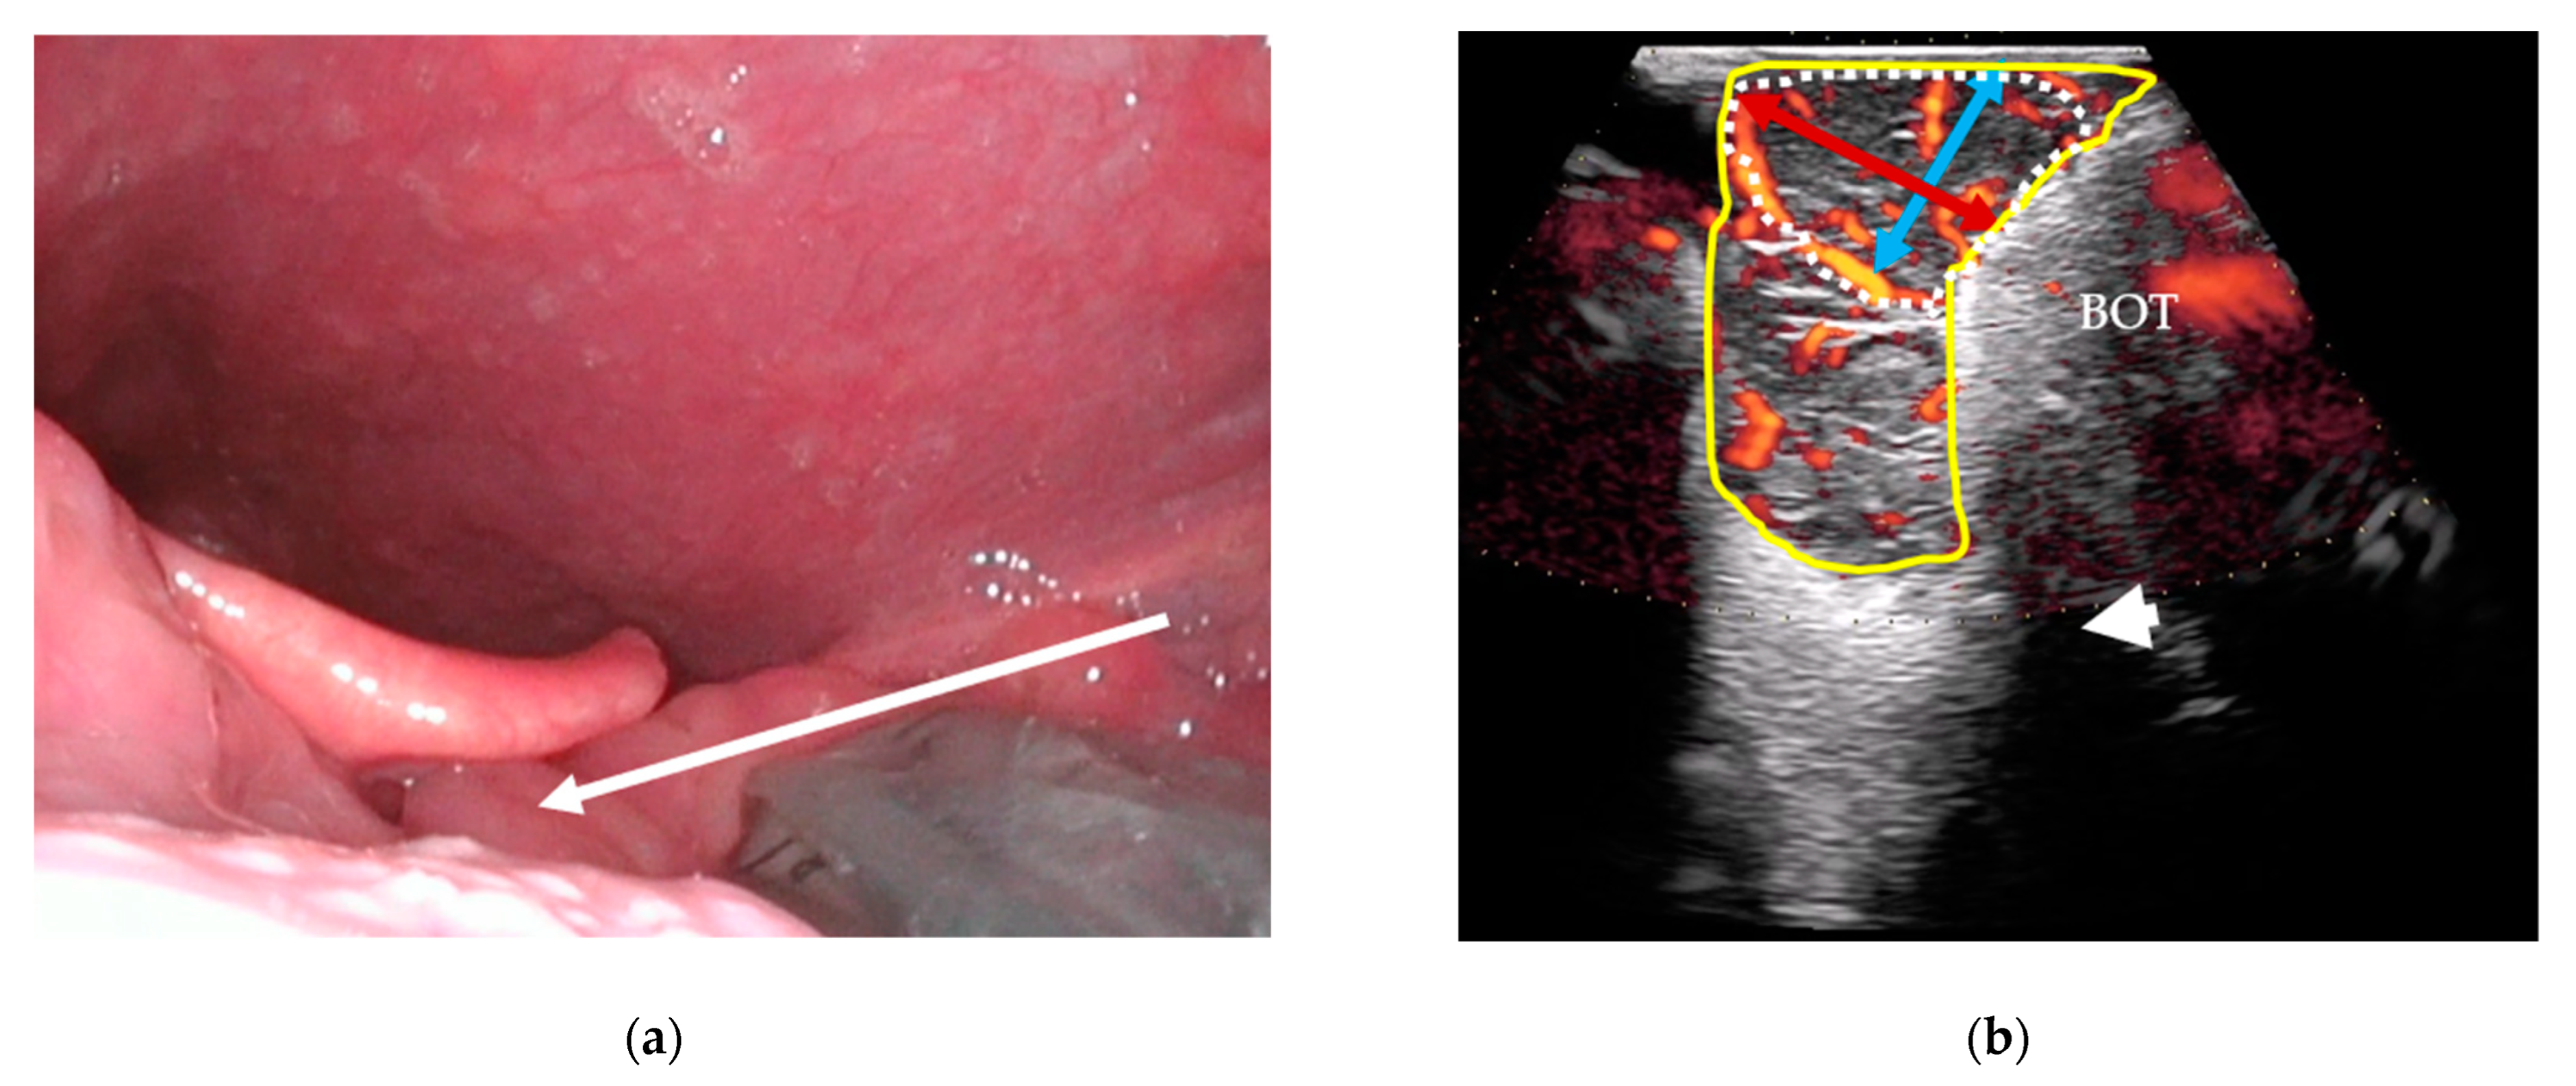

CTs and MRIs will be evaluated for the greatest tumor diameters in three dimensions (craniocaudal, anteroposterior, and mediolateral) for visible tumors. Tumors will be measured in three perpendicular dimensions in axial (anteroposterior and mediolateral diameters) and coronal/sagittal planes (craniocaudal diameter) (Figure 4). A categorical T-stage will be estimated using CT and MRI according to the UICC8 staging system.

Figure 4. Contrast-enhanced, T1-weighted MRI images of a stage T1 squamous cell carcinoma of the right palatine tonsil: (a) axial orientation showing the mediolateral (yellow bi-directional arrows) and anteroposterior (red bi-directional arrows) diameters of the tumor; (b) sagittal orientation showing the craniocaudal (blue bi-directional arrows) diameter of the tumor.